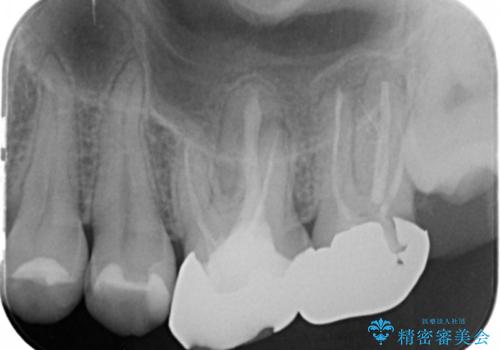

奥歯から臭いがする 銀歯下の虫歯再発

- 半年前から奥歯から嫌な臭いがする、と治療を求めて来院されました。

銀歯を除去したところ、虫歯が大きく再発しこのままではかぶせ直しができないような状況でした。

・根尖性歯周炎 →精密根管治療